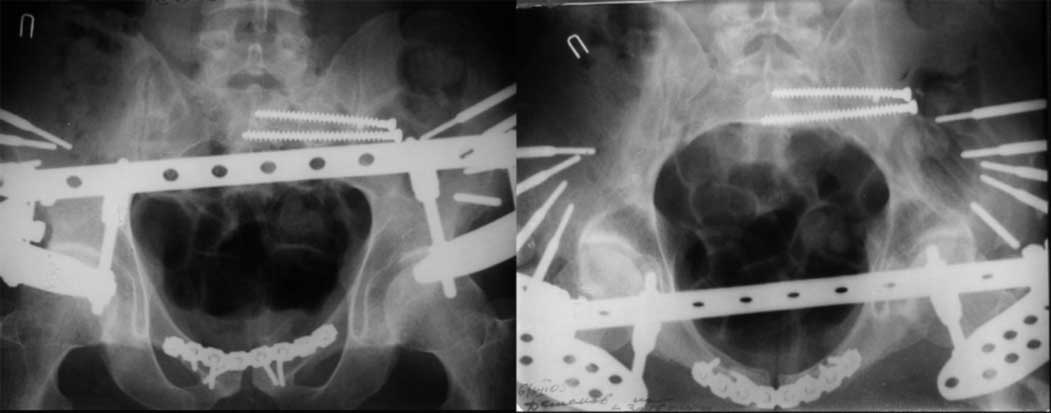

Дорогой Андрей. Мы имеем дело с комбинированной (ротационно и вертикально) нестабильностью таза со смещением правого гнемипелвиса. При таких переломах, фиксация только переднего полукольца вне зависимости от метода фиксации, как уже было сказано Djoldas Kuldjanov, M.D., не может создать адекватной фиксации. И перелом пластины был вполне ожидаемым после активизации пациента. Смещение сохраняется, и по-видимому не 2 см., а все 4, если не более. Разница всего (+2 см) по конечностям как вы указываете, скорее скомпенсировано позвоночником и протезом. Дополнительные снимки или КТ исследование помогли бы уточнить степень смещения с точностью до мм., выявить перелом поперечного отростка пятого поясничного позвонка, или помимо разрыва правого крестцово-подвздошного сочленения выявить перелом боковой массы крестца справа и т.д. При возможности, конечно, все это желательно сделать. Но мало что изменится с практической точки зрения, т.к. задача - это низведение репозиция и надежная фиксация правого гемипелвиса. Учитывая плачевный опыт стержневого аппарата, давность травмы совершенно очевидно, что поставленная задача достижима при открытой репозиции и одномоментной фиксации переднего полукольца с артродезированием правого крестцово-подвздошного сустава. Операция выполняется в положении больного на здоровом боку или полубоку из расширенного трансоссального подвздошно-пахового доступа с переходом на лонное сочленение доступом по Pfannenstiel. Указанный доступ обеспечивает подход к крестцово-подвздошному сочленению как спереди так и сзади. После артродезирования выполняется синтез лонного сочленения. Клинический пример

23.09.2003. Одновременный остеосинтез переднего и заднего тазовых полуколец

Результат через 10 дней

и 8месяцев после операции